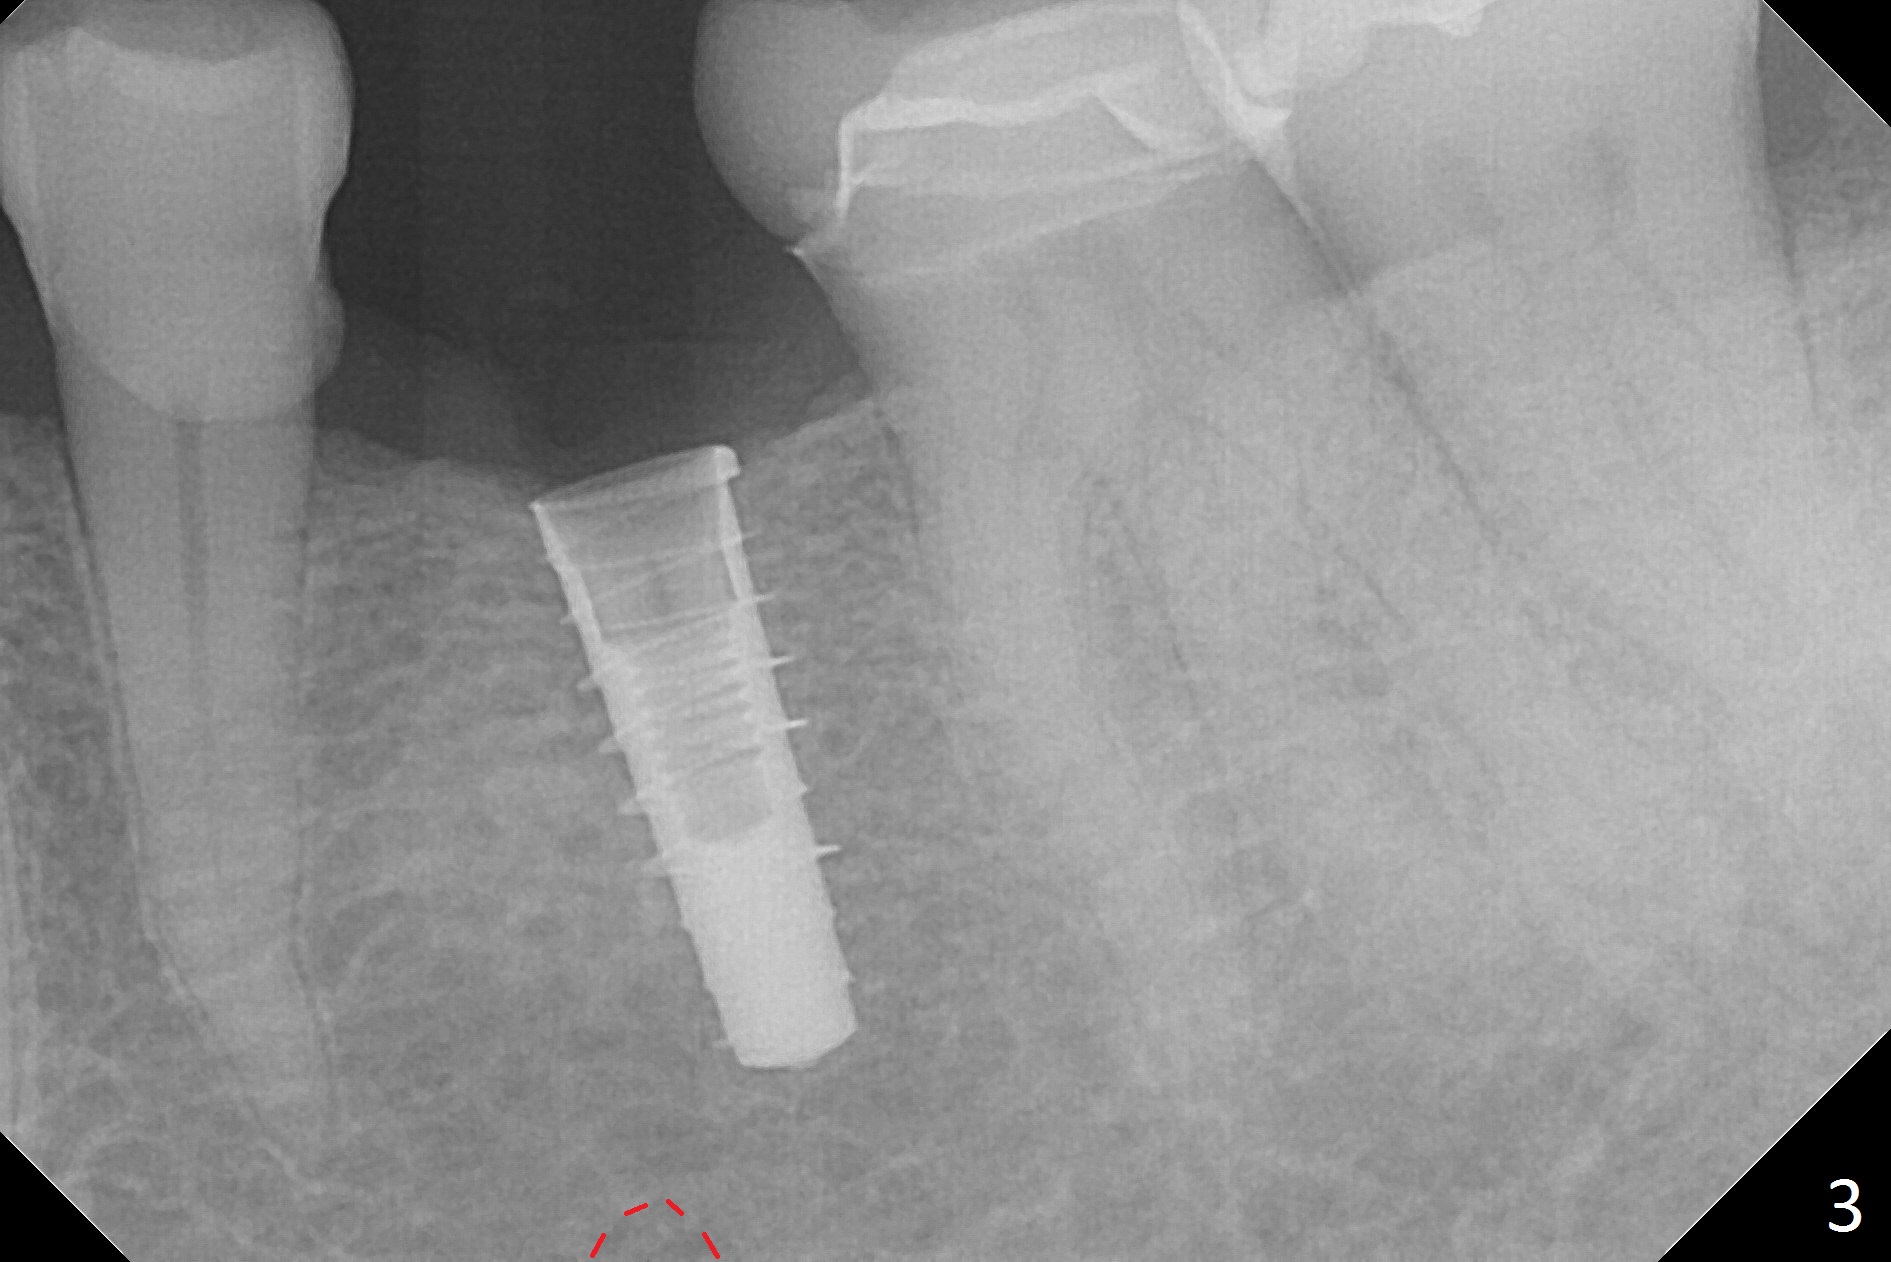

Initial osteotomy with 1.6 mm drill for 11 mm seems to be distal (Fig.1). The trajectory should be changed as shown by the black line in Fig.2; the drawback would be close to the Mental Loop (red line). Fortunately the trajectory is changed, but not so much as to be close the Loop when a 4x11 mm dummy implant is placed (Fig.3). When a 4x13 mm IBS is placed with 46 Ncm, there is clearance from the Loop (Fig.4-6). In fact there is no postop paresthesia. The main point is no block anesthesia. Infiltration anesthesia is administered with 34 mg Xylocaine with 17 mcg Epinephrine. The patient experiences dull pain when the implant is placed (Fig.4-6). After further anesthesia with 68 mg Septocaine, 17 mcg Epinephrine, the implant is torqued for a few turns (still with some discomfort). Finally autogenous bone with Osteogen is placed around the implant following placement of a 4.5x4(2) mm abutment. To reduce anxiety, a shorter implant should have been used. The patient complains of cold sensitivity in the lower left quadrant 4 months postop (Fig.7): the implant apparently close to the Mental Loop. Without an immediate provisional, the gingiva around the abutment is healthy.